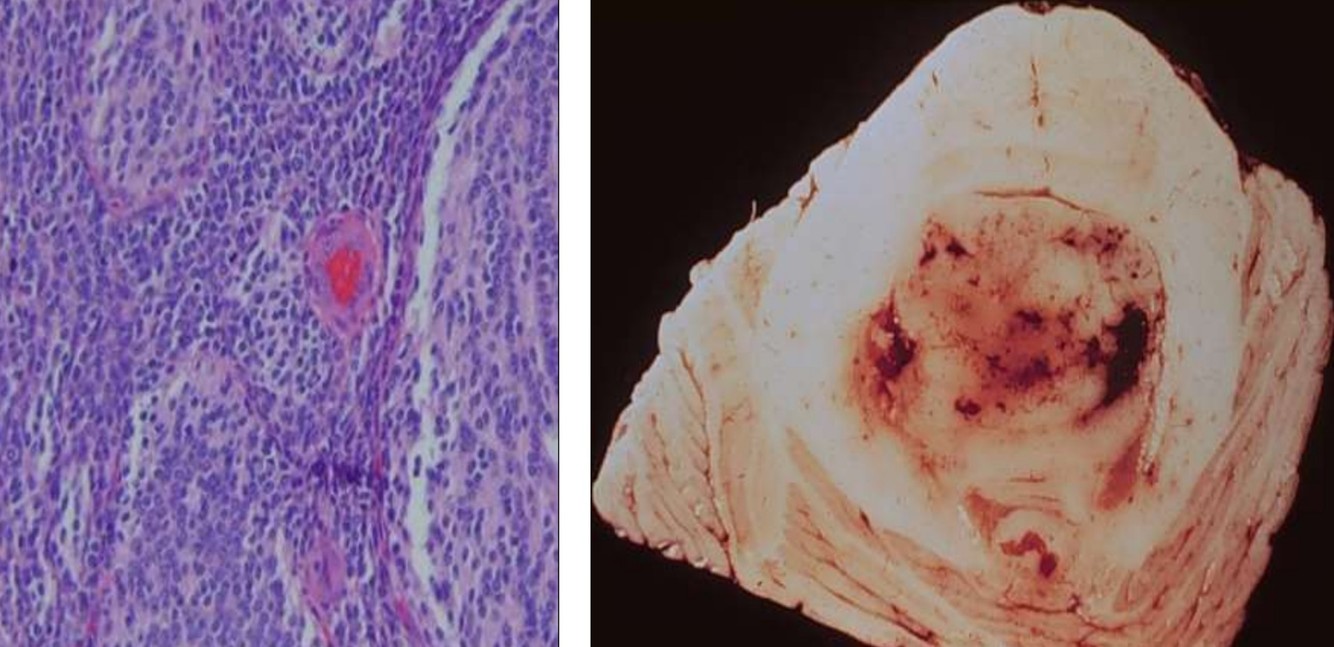

Meningioma

- Benign tumors of adults

- Locations:

- Attached to dura, arise from arachnoid meningothelial cells

- Intraventricular, arise from stromal arachnoid cells of choroid plexus

- Slight female predominance (3:2)

- Often express progesterone receptors

- Rapid growth during pregnancy

- Cytogenetics

- loss of chromosome 22q

- Multiple meningiomas associated with NF2

Meningioma Grades and subtypes

Meningioma Grades and subtypes

- Grade I (92%): most common, “cure” possible with complete resection

- Meningothelial, fibrous, transitional, psammomatous, angiomatous, microcystic, secretory, lymphoplasmacyte-rich, mataplastic

- Grade II (7%): higher rate of recurrence

- Atypical, clear cell, chordoid

- Grade III (rare): highly aggressive

- Anaplastic, rhabdoid, papillary

Anaplastic Meningioma

Clear Cell Meningioma